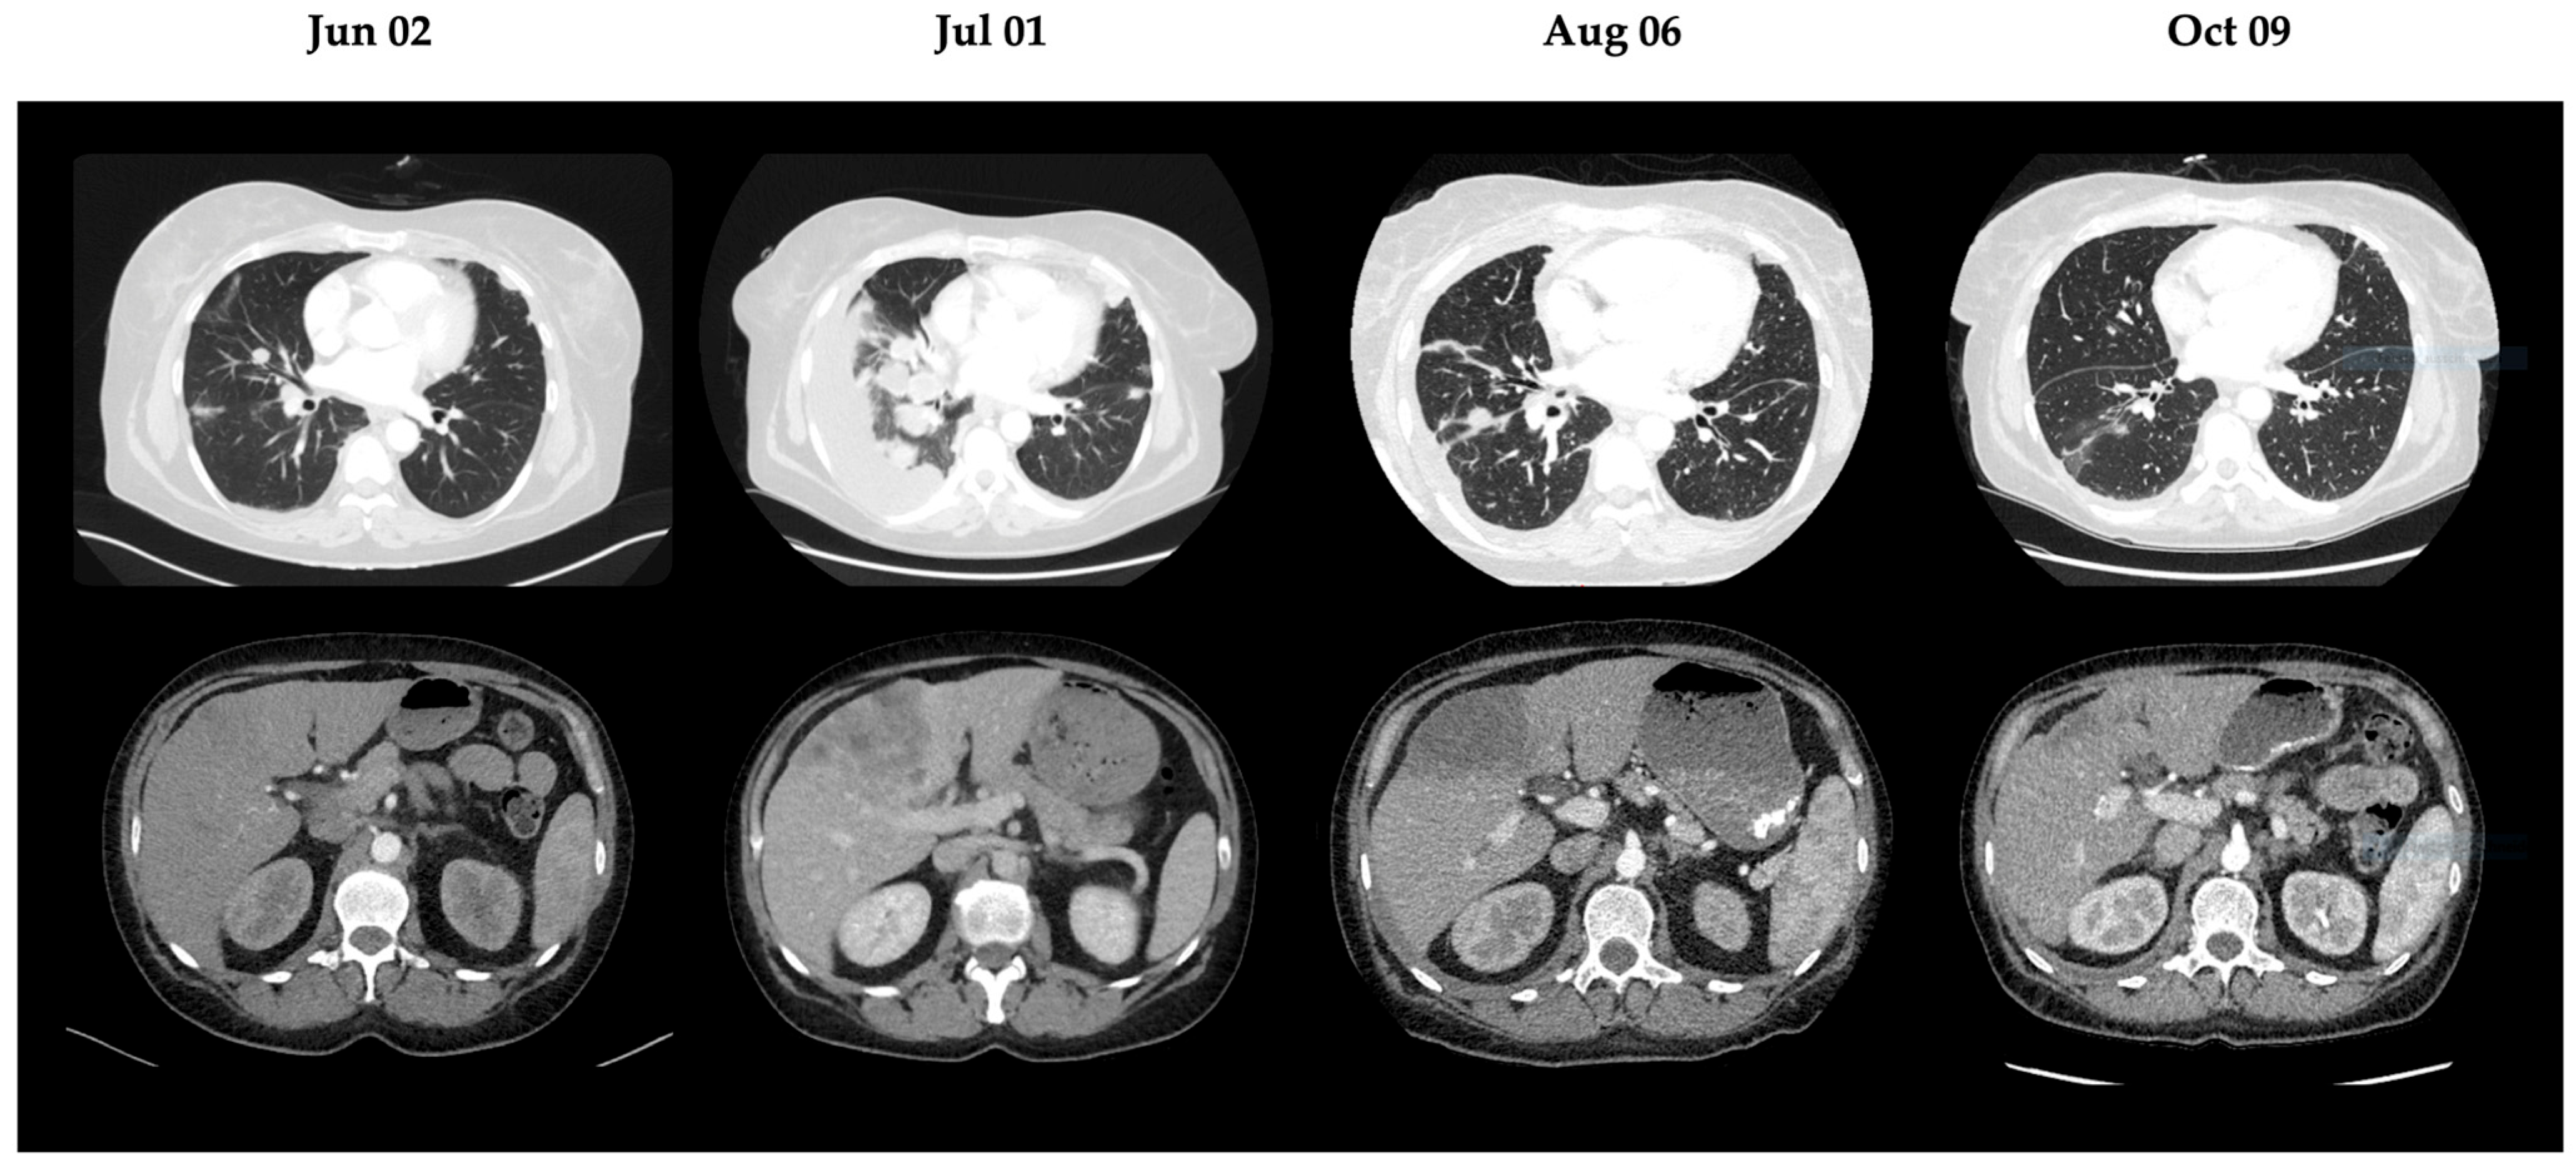

| 12 November 2024 | CT thorax/abdomen | Progressive disease NGS testing: MET amplification as secondary resistance Start cisplatin/pemetrexed |

| 1 July 2025 | CT thorax/abdomen | Progression of pulmonary tumors and hepatic metastases |

| 6 August 2025 | CT thorax/abdomen | Regression of pulmonary tumors and hepatic metastases |

| 9 October 2025 | CT thorax/abdomen | Further regression of pulmonary tumors and hepatic metastases |